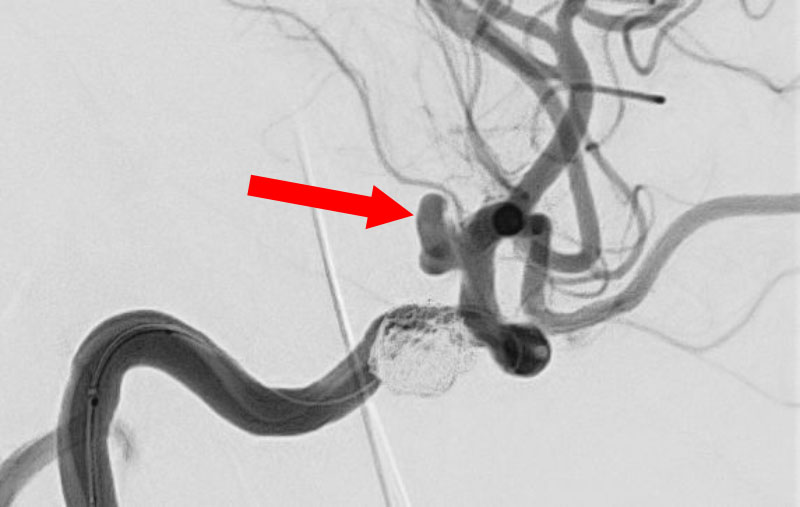

No.1596 手術中